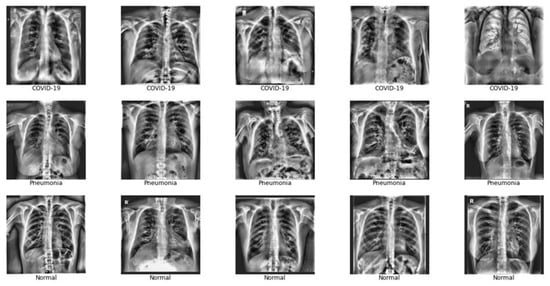

A total of 3330 CXRs were used to train and test the CNN models. Each CXR corresponded to a unique patient. The training and testing dataset contains 632 images of COVID-19+ patients, 1592 images of healthy patients, and 1106 images of patients with non-COVID-19 pneumonia. Considering that normal images significantly outnumbered both pneumonia and COVID-19 images, the 1592 normal images were chosen at random from all images that could have been included. An additional 836 images were kept for validating the ensemble model, of which 160 were COVID-19 images, 406 were of healthy patients and 269 belonged to patients with pneumonia. The count of CXRs is shown in Table 1. The three classes of images will be referred to as COVID-19, normal, and pneumonia, respectively for the rest of the paper. Example CXRs are shown in Figure 2.

Figure 2.

Sample of COVID-19, pneumonia and normal CXRs used in training and testing the model.